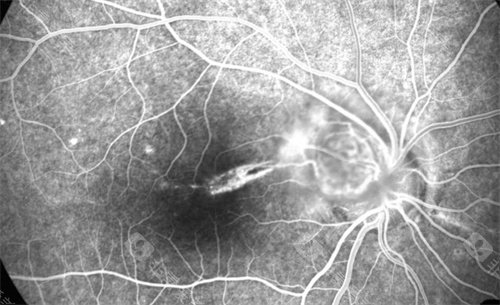

眼底病变

眼底病示意图

眼底病症状示意图

眼底病图谱示意图

眼底病包括的疾病示意图

眼底地形图